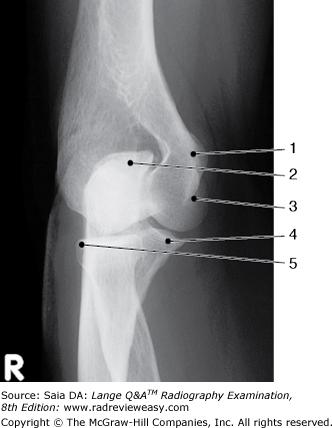

Which of the following is (are) accurate positioning or evaluation criteria for an AP projection of the normal knee?

A 1 only

-In the AP projection of the normal knee, the space between the tibial plateau and the femoral condyles is equal bilaterally. It is, therefore, important that there be no pelvic rotation that could change the appearance of an otherwise normal relationship. The AP projection of the knee superimposes the patella and femur. The CR should enter at the knee joint, located ½ in. distal to the patellar apex.